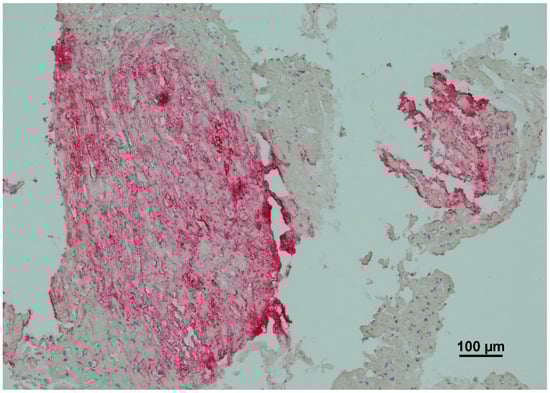

Immunohistochemistry (IHC) is a key diagnostic tool in amyloidosis, allowing for the identification and classification of specific amyloid subtypes through antigen–antibody interactions. The technique uses monoclonal or polyclonal antibodies that bind to unique epitopes on amyloidogenic proteins, enabling targeted detection of amyloid deposits within tissue sections (Figure 2). The tissue is first fixed in formalin, embedded in paraffin, and sectioned into 4–6 µm slices. Following deparaffinization and rehydration, antigen retrieval, via heat or enzymatic digestion is performed to expose hidden epitopes [38,39]. Primary antibodies are applied to target specific amyloid types, such as light chains (κ, λ), transthyretin (ATTR), or serum amyloid A (AA). Secondary antibodies, conjugated to enzymes or fluorophores, bind to the primary antibodies and produce a signal-either chromogenic (color precipitate) or fluorescent (visible under a fluorescence microscope). IHC enables differentiation between amyloid types: κ/λ light chains for AL amyloidosis, transthyretin for ATTR, and serum amyloid A for AA. It also supports identification of rarer subtypes using antibodies against apolipoprotein A, gelsolin, or β2-microglobulin [40]. Despite its diagnostic value, IHC has limitations. These include antibody cross-reactivity, reduced sensitivity due to epitope masking from formalin fixation, and a limited antibody panel. It is also semi-quantitative and can be affected by inter-laboratory variability. However, recent improvements such as multiplex IHC, automated staining platforms, and digital pathology have enhanced the accuracy, consistency, and efficiency of amyloid typing using this method [41].

Figure 2.

Immunohistochemistry (IHC) typing of AL amyloidosis. The red chromogen indicates positive antibody binding specifically to light-chain deposits within the amyloid nodule. The staining pattern is heterogeneous but specific, the intense red coloration is restricted to the amyloid aggregates, while the adjacent myocardial tissue remains unstained, confirming that the pattern represents specific antigen–antibody interaction within the infiltrates rather than a diffusion artifact.